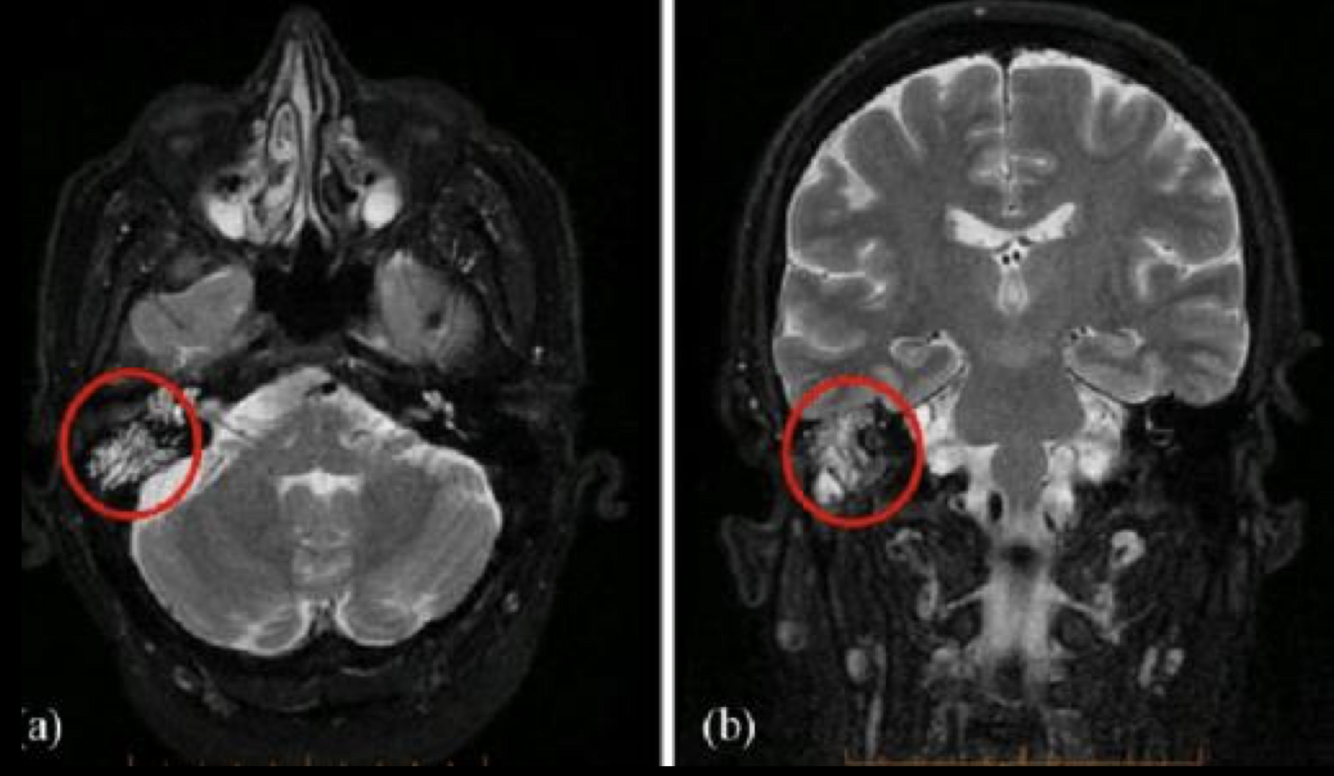

10

A

RM mastoiditis